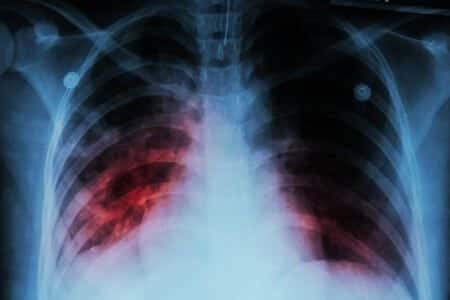

This case takes place in Florida and involves an obese man who fractured his ankle, which was repaired through surgery performed by a podiatrist DPM physician. A few weeks after undergoing the operation, the patient presented to the podiatrist’s office for a follow-up visit. During the appointment, the man complained of persistent shortness of breath, which had persisted since the date of the operation. The podiatrist performed three checks of the patient’s heart during his exam, with each check revealing tachycardia. In addition, some swelling of the patient’s leg was noted and documented by the podiatrist. The defendant physician advised the patient to see his family doctor before clearing him for anesthesia, which would have been required to remove orthopedic hardware that had been installed in his ankle. Despite these worrying signs, the patient was not told to go the emergency room. As a result, the patient died from a pulmonary embolism within 48 hours of seeing his podiatrist.

The podiatrist DPM performed a prior surgical procedure on his ankle, but a podiatrist is not a trained medical doctor that can offer appropriate therapy in the event of a dangerous clotting risk. The surgery was performed on his ankle - this is not an anatomical location associated with deep veins thrombosis where the 'clot' likely originated. The patient was obese as well, which represents a risk factor in itself. The podiatrist could have advised an immediate ER visit but a legitimate alternative was to refer him to a primary care physician who is knowledgeable in initiating appropriate treatment for this risk. Regarding accepted standard medical care, a physician (not the podiatrist) would have ordered an emergency CT angiogram required to document the pulmonary embolism. An oxygen saturation might have displayed hypoxemia, but the oximeter is usually not a 'standard' medical device in a podiatrist's office. Again, there are specific medical approaches necessary for diagnosing a deep vein thrombus, and these necessitate special expertise for treatment. Even if the podiatrist referred the patient to an ER, another physician would have been responsible for treatment. The mortality rate for undiagnosed pulmonary embolism is high, but a podiatrist is not trained to treat or manage them.